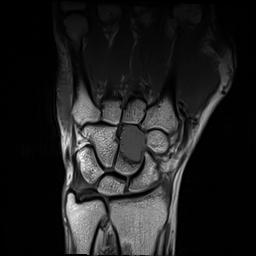

Myeloma Bone Disease

Myeloma in hand

MRI (with contrast or STR images) very useful to delineate problems

MRI and FDG-PET in Multiple Myeloma

• > 3 focal lesions or SUV > 4.2 at diagnosis results in shorter PFS and OS[1]

• 65% of pts PET/CT negative 3 mos after ASCT with longer PFS and OS vs PET positive[1]

• Complete FDG suppression associated with durable disease control and prolonged OS[1]

• Skeletal survey recommended in cases of plasmacytoma, extramedullary disease, suspected spinal cord compression as well as with new symptoms or progression[2]

• MRI and/or PET/CT indicated when symptomatic areas show no abnormality on radiograph[3]

1. Zamagni E, et al. Blood. 2011;118:5989-5995. 2. Ludwig H, et al. Leukemia. 2014;28:981-992. 3. NCCN. Clinical practice guidelines in oncology: multiple myeloma. v.2.2014. 4. Boot M, et al. Novel prognostic modalities in multiple myeloma. 2013. MRI FDG PET Imaging Techniques[4]